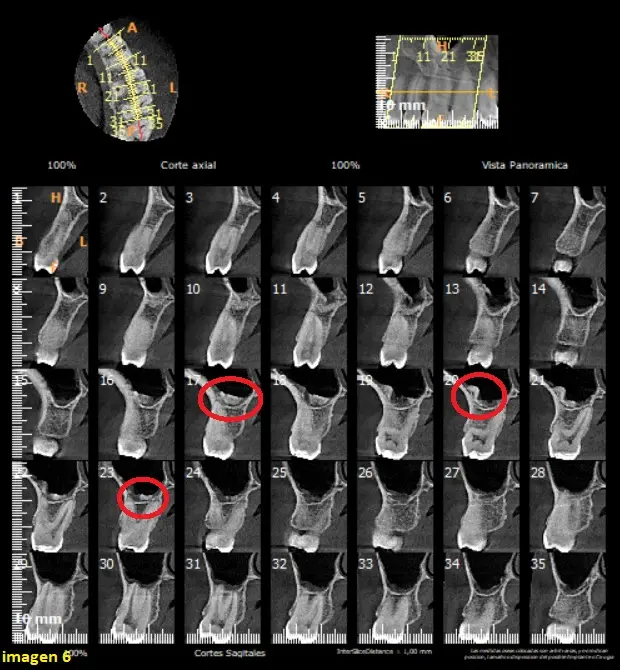

En el corte tangencial del seno maxilar izquierdo, hacia nivel vestibular, podemos observar la calcificacion sobre la raiz de la pieza dentaria 26 (circulo) y un leve engrosamiento de la membrana sinusal del seno (flecha blanca) (ver imagen 4)